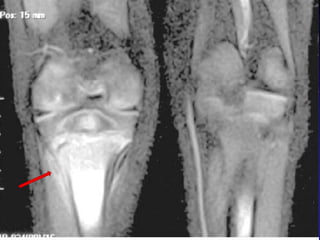

Focus of abnormal signal intensity in middle

one third of proximal femoral epiphysis.

Case-6 A 12y old female patient, had hx of chronic pain left knee, limping of 14 m . She used to wake up at night from the pain, she became a well known case to one of the hospital as pethidine addict patient. O/E: mild wasting of thigh muscles, full ROM both lower limbs with no focal tenderness.

• 116.